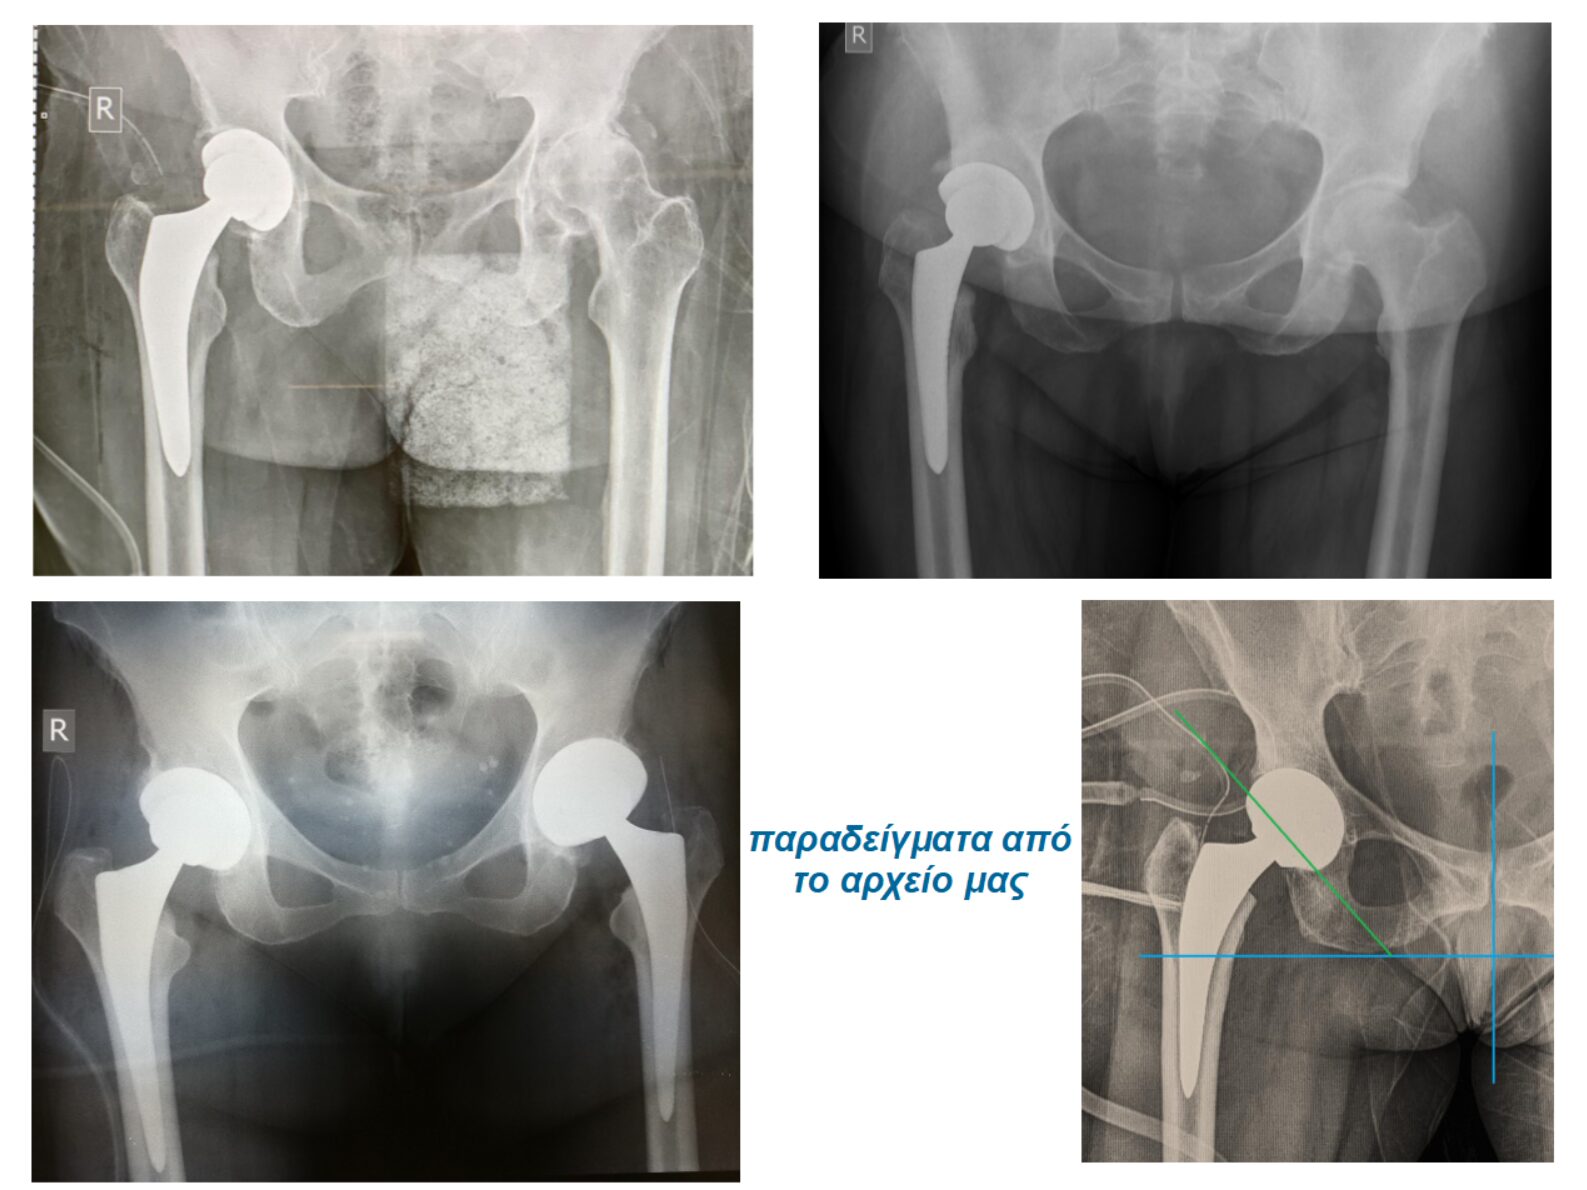

– Mελετήσουμε λεπτομερώς με τρισδιάστατη αξονική τομογραφία την ανατομία του πάσχοντος σκέλους

–  Πραγματοποιήσουμε εικονικά την επέμβαση στον υπολογιστή σε τρισδιάστατο μοντέλο

– Τοποθετήσουμε τις προθέσεις μας κατά την επέμβαση ΑΚΡΙΒΩΣ στην ιδανική γωνία – απόκλιση παρακολουθώντας συνεχώς σε ειδική οθόνη τις κινήσεις μας με ακρίβεια μίας μοίρας – ενός χιλιοστού.

Με τον τρόπο αυτό αναπαράγουμε με ακρίβεια αυτό που σχεδιάσαμε πριν την επέμβαση εμφυτεύοντας την αρθροπλαστική μας στην ιδανική θέση

Στην εικόνα 16 παρουσιάζεται ο σχεδιασμός   της αρθροπλαστικής σε περιστατικό της κλινικής μας: επάνω αριστερά η ανατομία του ισχίου πριν την επέμβαση, κάτω αριστερά η εικονική εμφύτευση της  κοτύλης. Επάνω δεξιά η εικονική εμφύτευση του μηριαίου στυλεού. Τέλος, κάτω δεξιά το “πάντρεμα”των δύο και το τελικό αποτέλεσμα.

Στην εικόνα 17, οι ενδείξεις της οθόνης  από το χειρουργείο της ίδιας ασθενούς, όσον αφορά τη θέση των εμφφυτευμάτων και η ακτινολογική επιβεβαίωση κατά τη διάρκεια της επέμβασης. Το αποτέλεσμα ήταν προβλέψιμο και άριστο

Στην εικόνα 6 βλέπουμε την προεγχειρητική ακτινογραφία άνδρα 56 ετών που υποβλήθηκε σε ταυτόχρονη αρθροπλαστική AMIS με navigation robotic assistance. Στην εικόνα 21 ο προεγχειρητικός τρισδιάστατος σχεδιασμός, αναλυτικά. Στην εικόνα 22 η πλοήγηση από το σύστημα διεγχειρητικά, με απόλυτη ακρίβεια και το άριστο τελικό ακτινολογικό αποτέλεσμα. Ο ίδιος ασθενής στην επανεξέταση, 24 μέρες μετά την επέμβαση στο ιατρείο.